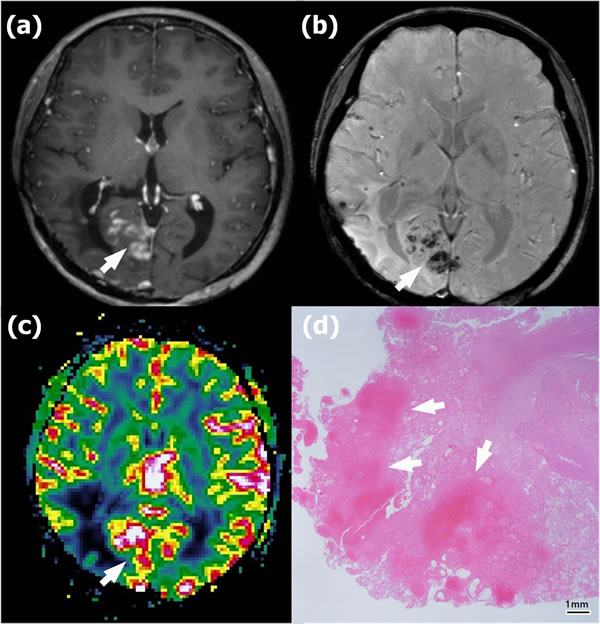

Figure 4: Radionecrosis in a 45-year-old woman with anaplastic astrocytoma in the right parietooccipital lobe who underwent gross total resection and concomitant chemoradiotherapy (CCRT). a. Contrast-enhanced T1-weighted (CET1) magnetic resonance (MR) image obtained 18 months after CCRT completion shows newly appearing multifocal enhancing lesions in the right occipital lobe (arrow). b. Susceptibility-weighted imaging demonstrates significant dark areas in the corresponding enhancing lesions (arrow); the proportion of dark signal intensity (proSWMRI) was 62.95 %. c. The normalized relative cerebral blood volume map (nCBV) from dynamic susceptibility contrast perfusion-weighted imaging shows increased blood flow in the corresponding enhancing area (arrow) (calculated 90th percentile points in the cumulative nCBV histogram (nCBV90) = 2.88). d. Hematoxylin-eosin-stained histopathology (original magnification, X 10) shows multiple hemorrhages of > 5 mm (arrows) within the radionecrosis.